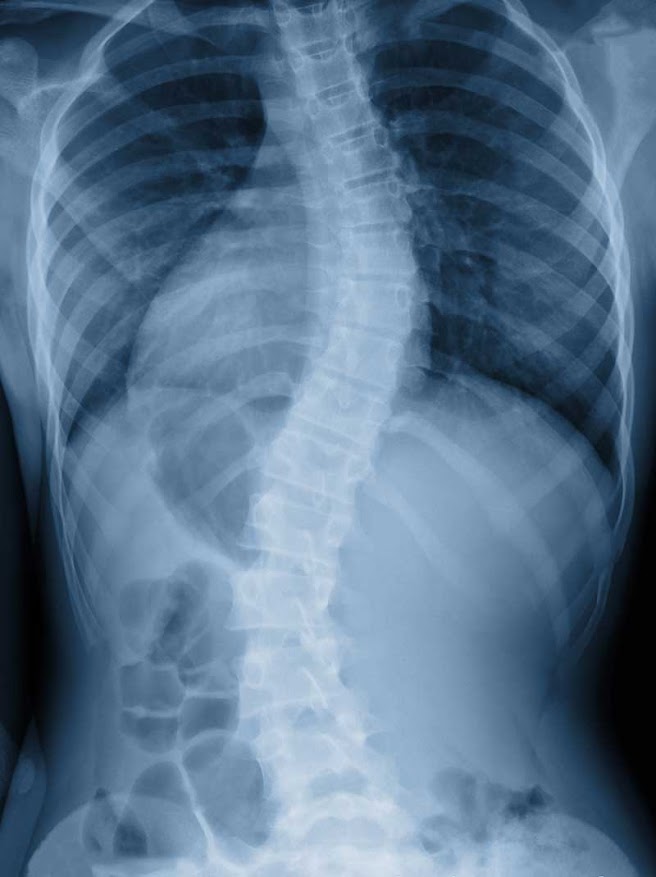

Scoliosis is an abnormal curvature of the spine that can cause pain, imbalance, poor posture, and physical limitations if left untreated. At ProRehab in San Marcos, we provide integrated, non-invasive scoliosis care that improves alignment, strengthens spinal support, and relieves symptoms, without the need for surgery or rigid bracing.

Scoliosis is a lateral (sideways) curvature of the spine, often shaped like an “S” or “C.” It may be structural (involving the vertebrae) or functional (due to muscle imbalance or posture). While mild scoliosis may go unnoticed, moderate to severe cases can cause visible misalignment and discomfort.